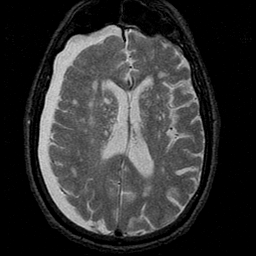

Subdural Hygroma,overlay -- Slice #28

[Home][Help][Clinical] Slice 28